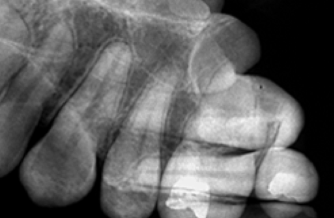

Herringbone Pattern

What it looks like:

A tire-track or fishbone pattern across the image.

Cause:

Film placed backwards.

Fix:

Place the white side toward the X-ray beam.